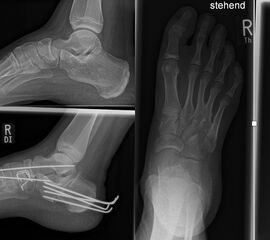

Abb. 2 a-c: offene Wachstumsfugen MT I Basis und Zehen (a), teilweise geöffnete Wachstumsfugen (b) und geschlossene Wachstumsfugen (c).

Zum Lesen der Bildbeschreibung und zur Vollansicht bitte die Bilder anklicken. Bilder: A. Helmers.